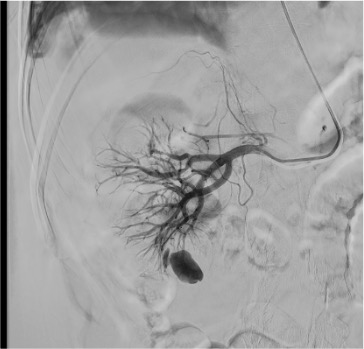

- AML vascularity: dysplastic, tortuous feeding arteries with microaneurysms; characteristic “onion skin” appearance of abnormal vessels

- Pseudoaneurysms: focal contrast pooling on angiogram; contained rupture of arterial wall — often at biopsy tract

On flush aortogram, identify renal artery origins at L1–L2 (tennis racket or Omni-Flush catheter positioned with tip just above renal artery origins). Selective renal angiogram defines anterior/posterior division and segmental branches. In the nephrographic phase, assess for parenchymal defects (prior infarcts), mass effect (tumor), and early venous filling (AVM/AVF). Superselective catheterization into the feeding segmental or interlobar artery using microcatheter allows precise identification of the target lesion before embolization.

Superselective Catheterization

Embolization